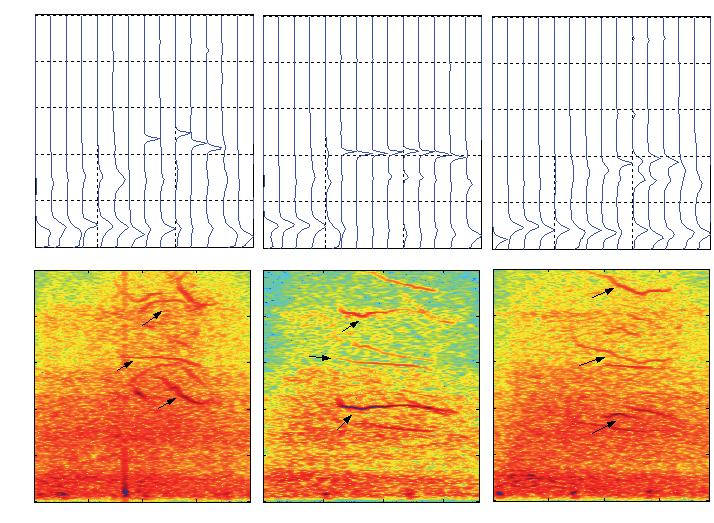

També per a una millor estimació dels PVT s’ha proposat un nou mètode basat en mapes espectrotemporals (figura 10), que facilita l’estudi de la seva forma i de la variabilitat batec a batec (Laciar i Jané, 2005).

IGURA 10.Mapes espectrotemporals per a la detecció de PVT en senyals ECG amb baixa relació senyal-soroll. s s

Amplitud mV) Freqüència (Hz) Amplitud mV) Freqüència (Hz) Temps (ms) Batec individual amb soroll Estimació mitjana del batec cardíac Temps (ms) Temps (ms)Temps (ms) Corr. creuada bidimensional Batec individual Temps (ms)Temps (ms) Freqüència (Hz) Freqüència (Hz) PVTPVT? PVT? PVT? PVT? , , , , , ,